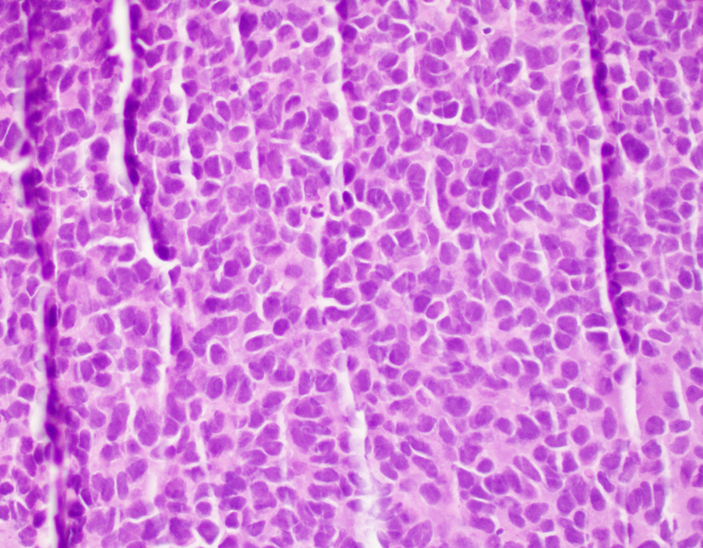

Microscopic (histologic) description

- Classical Ewing sarcoma (Virchows Arch 2009;455:397)

- Uniform small round cells

- Tumor cells 1 - 2x size of lymphocytes

- Round nuclei

- Finely stippled chromatin

- Inconspicuous nucleoli

- Scant clear to eosinophilic cytoplasm

- Indistinct cytoplasmic membranes

- Sheet-like growth pattern

- Islands separated by dense fibrous tissue

- Subset with neuroectodermal differentiation (Homer-Wright pseudorosettes)

Microscopic (histologic) images